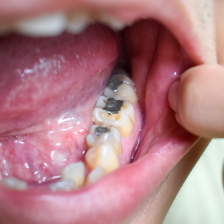

虫歯治療